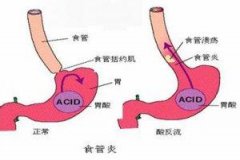

Barrett食管的病因

导语 食管下段的鳞状上皮被柱状上皮覆盖,称Barrett食管,又称巴雷特食管。